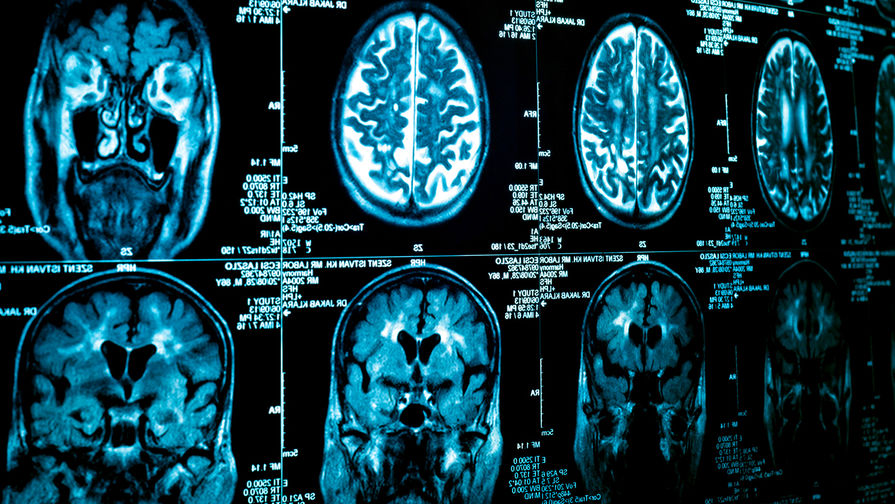

Мозг женщин в среднем на три года моложе мозга мужчин того же возраста, выяснили американские ученые. Они предполагают, что именно с этим связаны лучшие результаты пожилых женщин на память и мышление, а также их меньшая подверженность нейродегенеративным заболеваниям.

С возрастом мозг человека уменьшается, а метаболизм в нем замедляется. Однако, как выяснили исследователи из Вашингтонского университета, у женщин это происходит медленнее: их мозг остается в среднем на три года моложе, чем мужской. Об этом открытии ученые рассказали в журнале Proceedings of the National Academy of Sciences.

Участниками исследования стали 121 женщина и 84 мужчины в возрасте от 20 до 82 лет. Авторы работы с помощью позитронно-эмиссионной томографии изучили, как их мозг снабжается глюкозой и кислородом, и с помощью нейронных сетей выявили связь между метаболизмом мозга и возрастом мужчин. Затем, исходя из этих данных, алгоритм высчитал предполагаемый возраст женщин исходя из метаболизма их мозга.